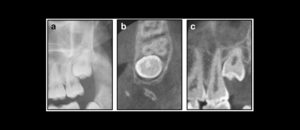

El objetivo del presente estudio fue evaluar los factores (referidos a la CBCT) que influyen en la toma de decisión en tratamientos para extracción de